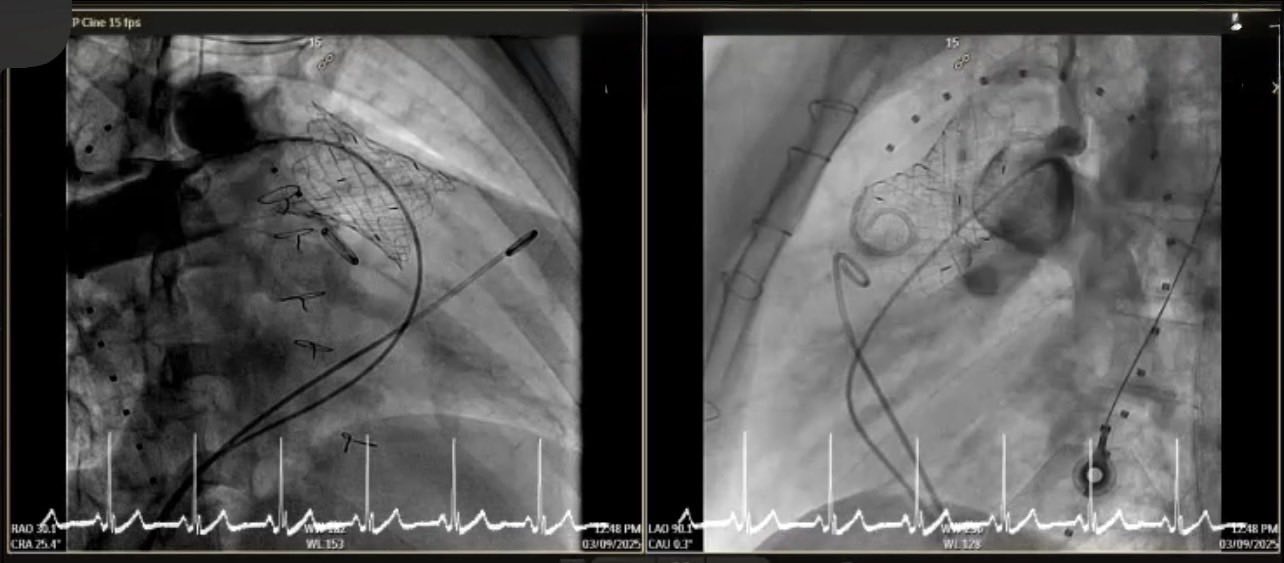

การใส่ลิ้นหัวใจพัลโมนิกเทียมผ่านสายสวนหัวใจ (Transcatheter pulmonary valve implantation; TPRI ) ในครั้งนี้ ทำผ่านทางหลอดเลือดดำใหญ่ บริเวณขาหนีบ จึงไม่ต้องผ่าตัดเปิดทรวงอก โดยกระบวนการรักษาและพักฟื้นผ่านไปได้ด้วยดี ไม่พบภาวะแทรกซ้อน ผู้ป่วยสามารถออกจากโรงพยาบาล 2 วันภายหลังการรักษา นับเป็นหนึ่งในความก้าวหน้าของนวัตกรรมการแพทย์เพื่อใช้รักษา ลดความเสี่ยงของภาวะแทรกซ้อนต่างๆ รวมถึงยกระดับคุณภาพชีวิตของผู้ป่วยได้

การผ่าตัดเปิดทรวงอกในแต่ละครั้ง จะก่อให้เกิดพังผืด (fibrous adhesion) เพิ่มความยากลำบาก และความเสี่ยงในการผ่าตัดมากขึ้น การรักษาผ่านทางสายสวนจึงเป็นทางเลือกที่จะลดความเสี่ยงนี้ลง อีกทั้งยังสามารถใส่ลิ้นพัลโมนิกเทียมชิ้นใหม่ทับแทนชิ้นเก่าได้ (valve in valve procedure)

การรักษาผ่านทางสายสวนครั้งนี้ได้รับความร่วมมือจากสหสาขาวิชาชีพ อาทิเช่น ศัลยแพทย์โรคหัวใจ ทรวงอก และหลอดเลือด กุมารแพทย์โรคหัวใจ อายุรแพทย์โรคหัวใจ วิสัญญีแพทย์ รังสีแพทย์ นักเทคโนโลยีหัวใจและทรวงอก รังสีแพทย์และนักรังสีการแพทย์ เจ้าหน้าที่และพยาบาลห้องสวนหัวใจ ห้องผ่าตัดศัลยกรรมทรวงอก หอผู้ป่วยวิกฤตศัลยกรรมหัวใจหลอดเลือด หอผู้ป่วยพิเศษ 5 พยาบาลหน่วยโรคหัวใจเด็กและผู้ใหญ่